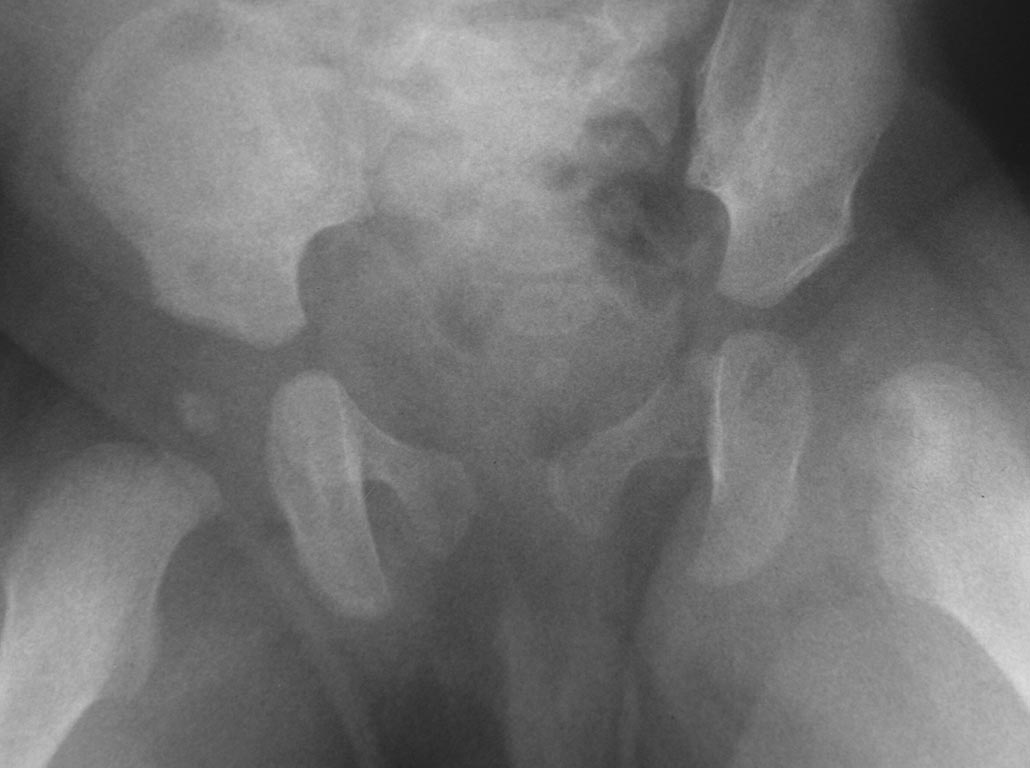

[Ortho] Острый гематогенный остеомиелит головки бедра и ребенка

Добрый вечер уважаемые коллеги. Помогите советом, в какую клинику и к

кому обратится с данной проблемой( у ребенка в возрасте 1мес.

диагностирован гематогенный остеомиелит головки бедра). Лечили

консервативно( выписку и фото в динамике прилагаю). На сегодняшний день

ребенку 11 мес. Детские ортопеды по месту сомневаются в тактике( в плане

операции или выжидательная тактика). Хотелось проконсультироваться с

теми кто занимается этой проблемой. Заранее спасибо.